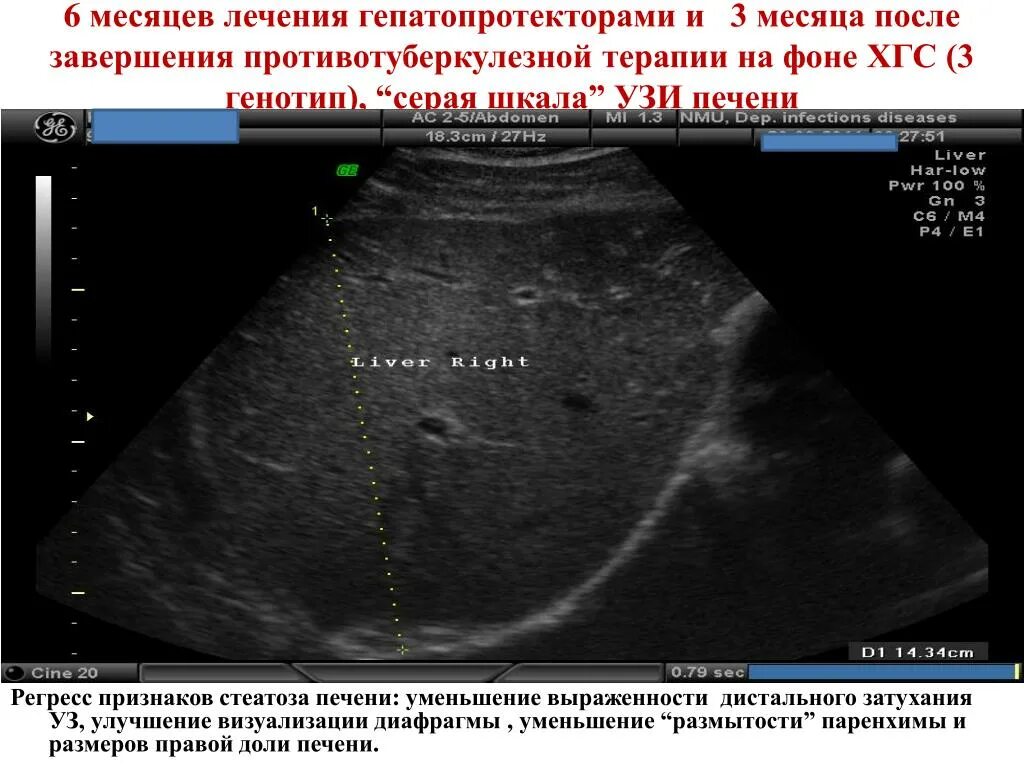

Анализ узи печени